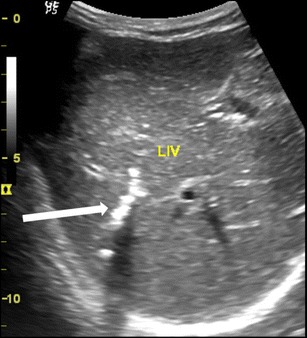

Intrahepatic ducts

Ascaris in the intrahepatic ducts are less common than the common bile duct. They may be seen in either lobes of liver with intrahepatic biliary dilatation. They are seen as similar tubular structures inside the hepatic ducts with a “strip sign” (Fig. 5a). On rare occasion, a “triple line” can also be appreciated on magnified view or with the use of high resolution linear array transducer (Fig. 5b). Calcified worms in the intrahepatic duct are also occasionally seen in asymptomatic patients on routine sonography (Fig. 6).

Fig. 5.

A 35-year-old female with acute pain in the right hypochondrium. (a) Ascaris seen in the left dilated intrahepatic duct (white arrow) and (b) magnified view of the ascaris in the dilated left intrahepatic duct, triple line seen (white thick arrow)

Fig. 6.

A 40-year-old female showing calcified shadow indicating calcified worms in the intrahepatic duct of the right lobe of liver (thick white arrow)